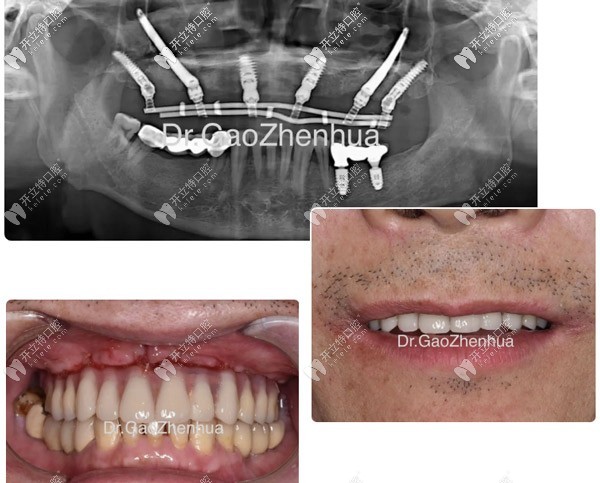

上海鼎植口腔種半口牙采用速齒種植、微創(chuàng)種植、數(shù)字化導(dǎo)板種植、即刻種植、即刻負(fù)重種植、機(jī)器人種植等技術(shù)。

目前上海鼎植口腔中半口牙技術(shù)好的醫(yī)生有:黎強(qiáng)、高振華、謝正新、李君首、張永新等院長。m.gh0097.com

上海永博口腔門診部高振華

高振華

擅長:種植牙